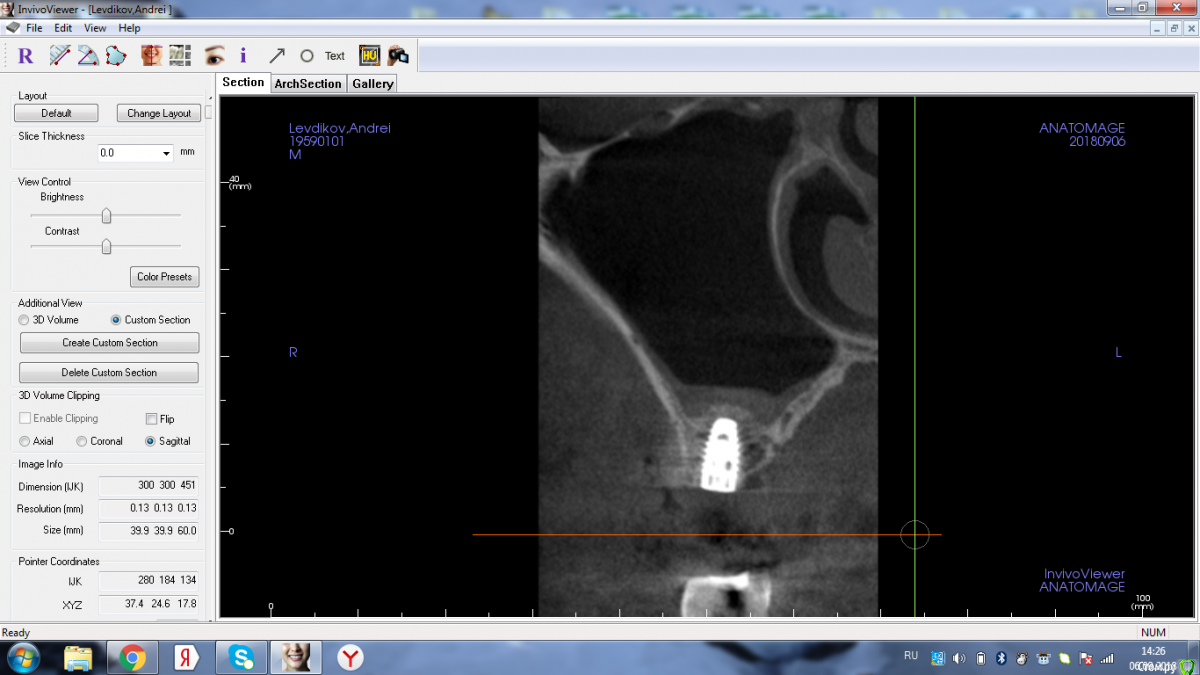

Shakirbura Опубликовано 6 сентября, 2018 Поделиться Опубликовано 6 сентября, 2018 Сегодня в первый раз попробовал. Мембрану не порвал. Пока гонял раствором хорошо ощущал напряжение. Ушло 1,5 колапола и и carrier апатоса. 3 Ссылка на комментарий